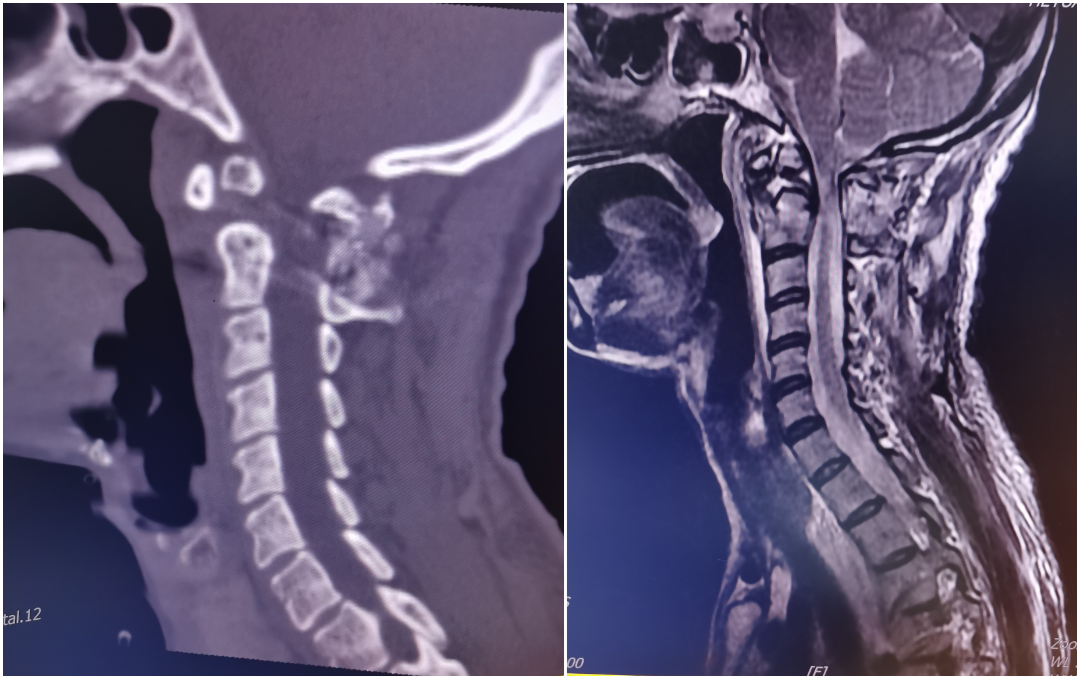

患者何某,中年女性,陈旧性枢椎齿状突骨折并寰枢关节脱位(难复性),入院是四肢不全瘫,生活不能自理;术前经大重量颅骨牵引不能复位(图三),于全麻行单一后路切开松解、寰椎后弓部分切除减压、经自制“Z”形复位棒复位、椎弓根螺钉内固定,术中透视见寰枢关节脱位完美复位,术后患者疾病症状改善。

术前影像:枢椎此状图陈旧骨折并寰枢关节脱位、脊髓明显受压